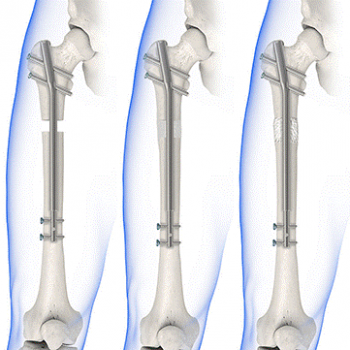

con clavo Precice

con clavo Precice

Última tecnología

El nuevo clavo Precice es el dispositivo de alargamiento más avanzado disponible en la actualidad. El clavo Precice tiene un excelente control de la tasa de alargamiento y los pacientes que han sido tratados mediante ambas técnicas (precice vs fijador externo) refieren una disminución significativa del dolor y discomfort.